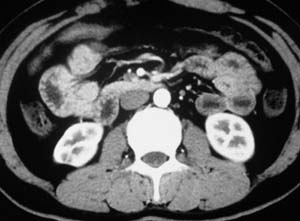

以下是引用子期在2010-3-19 20:47:00的发言:[br]血管畸形的ct增强应该有明显强化,本例并不相符合。本例双肾局部的略低密度影,累及肾盂,局部皮质明显变薄、内陷,增强扫描有轻度的强化,应考虑为炎性病变,患者为年轻男性,累及双肾的感染以结核较常见,可以没有明显的临床症状,尿中有时候也并不能查出什么;肾脓肿常有明显感染中毒症状,本例不符,另外一般的肾盂肾炎或肾小球肾炎通过小便就可确诊,其它还不能排除的是黄色肉芽肿性肾盂肾炎,然而单凭ct一般也很难鉴别。